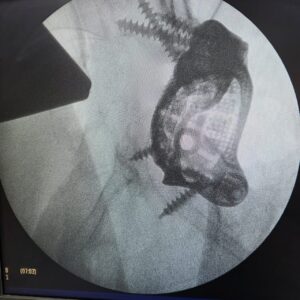

Postoperative Outcome: Stable Fixation After Complex Hip Revision

The implant was successfully placed in the appropriate position.

Postoperative imaging confirmed coverage of the defect and implant fixation.

This case demonstrates the application of a patient-specific FTL cup in managing a complex acetabular defect.

The use of CT-based planning and a customized implant enabled precise reconstruction in the presence of significant bone loss and structural deficiency.

Post-operative outcomes indicated stable implant positioning and enhanced functional recovery, supporting the clinical value of patient-specific solutions in complex hip reconstruction cases.